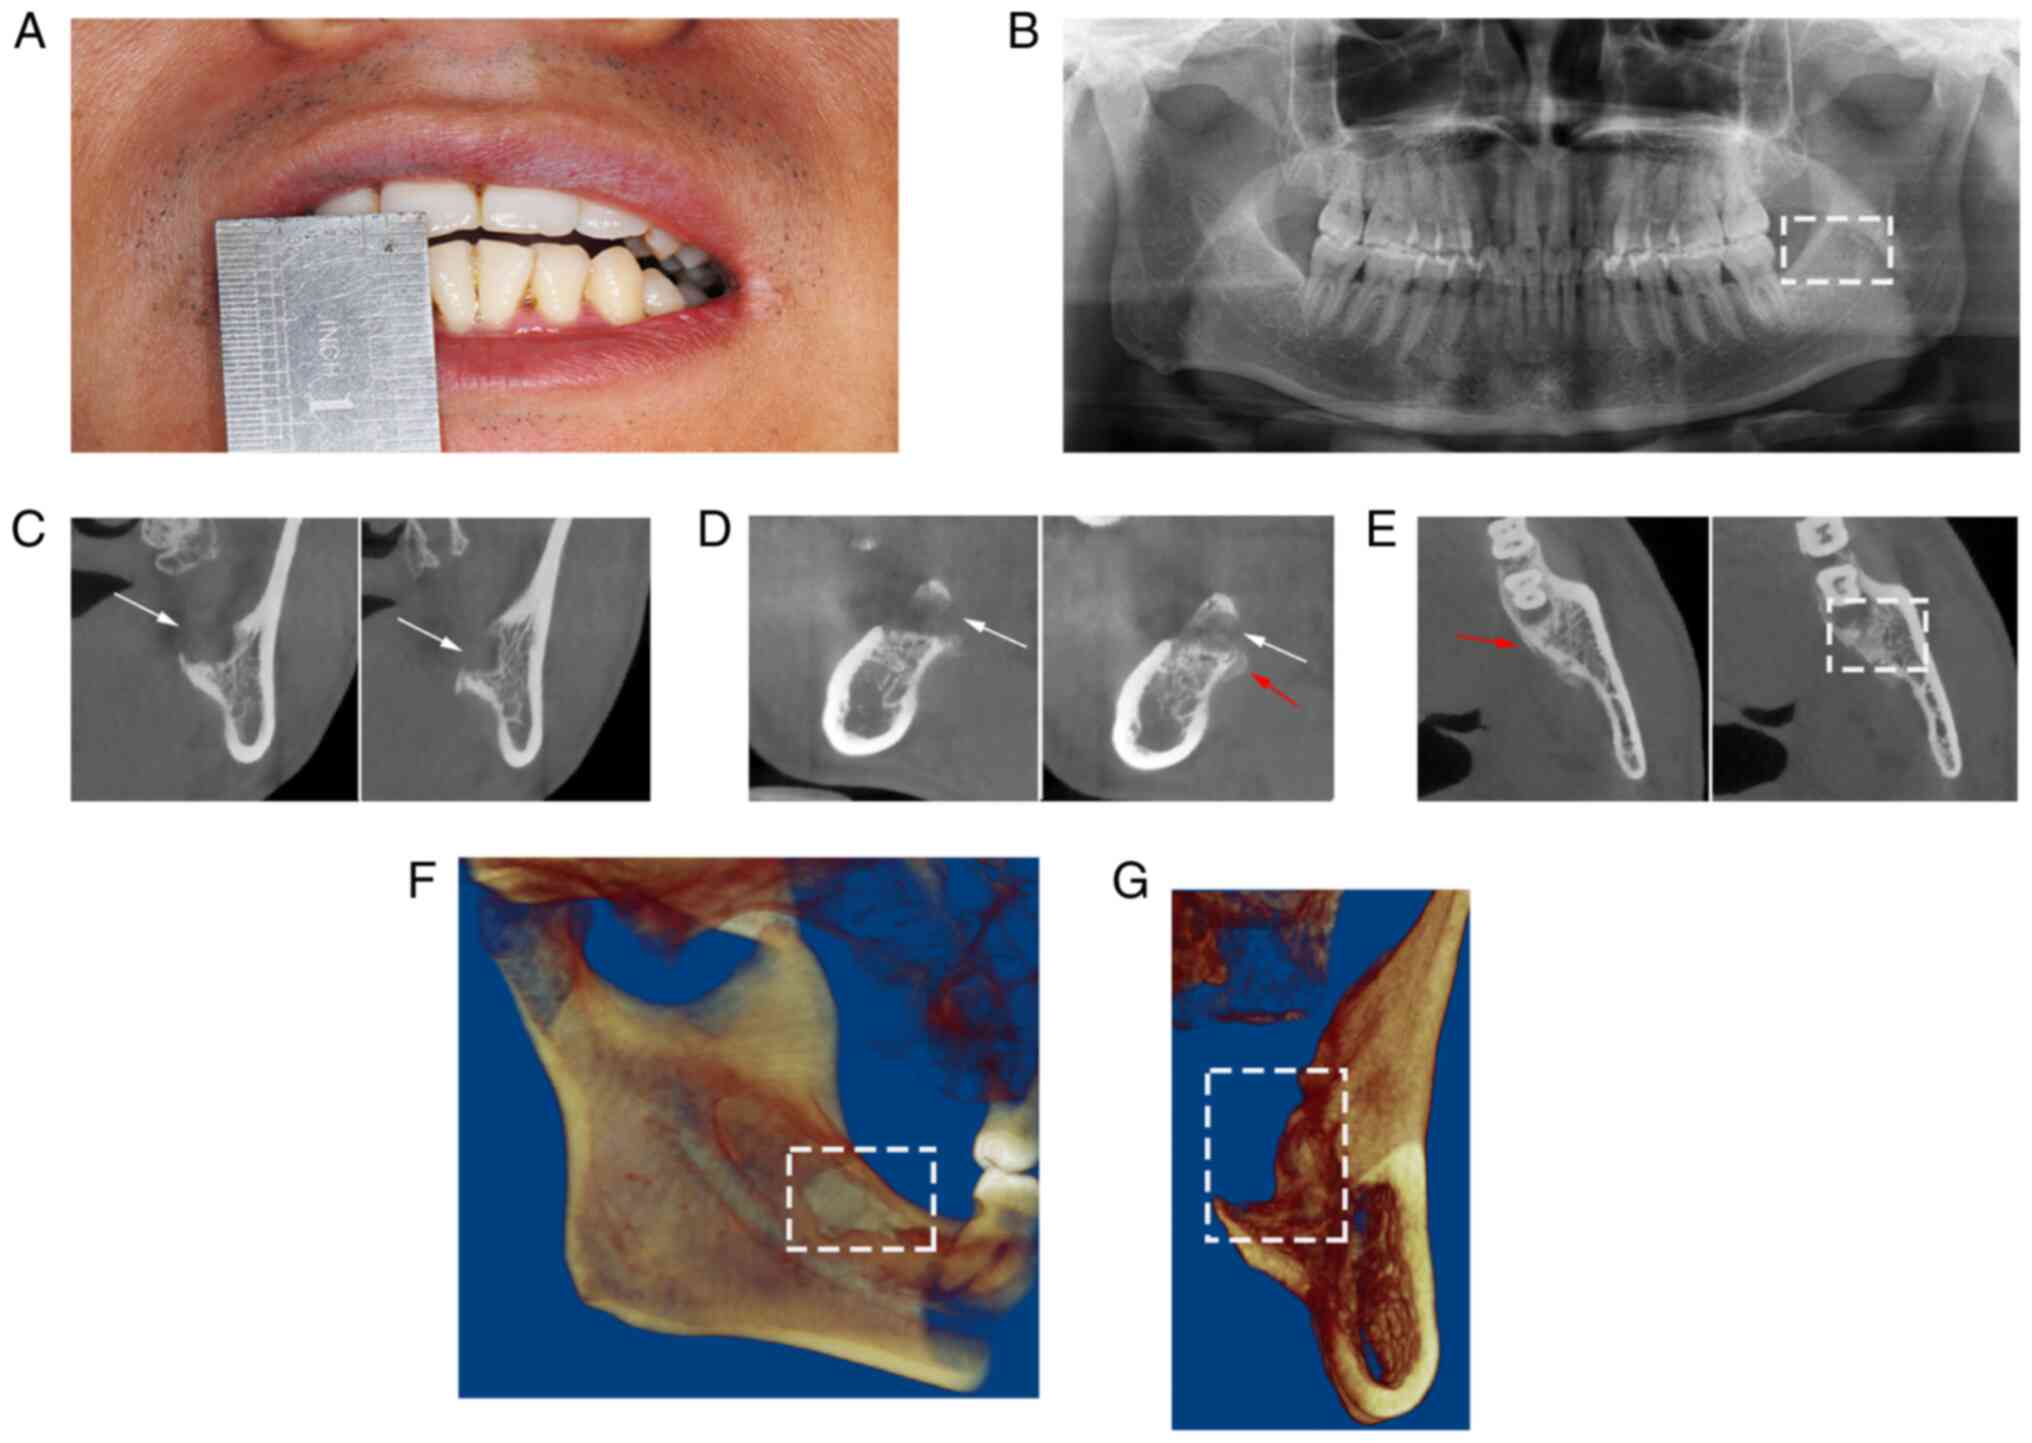

Persistent trismus following mandibular third molar extraction and its management: A case report and literature review

Trismus is one of the common complications which occur following the extraction of mandibular impacted third molars. This generally occurs due to low‑grade infection, repeated muscle stimulation, as well as other causes. This symptom is usually relieved after 1 to 2 weeks; however, it may persist for >1 month post‑operatively in very rare cases. The present study reports the case of a patient with trismus at 45 days following mandibular third molar extraction. The patient received local and systemic anti‑inflammatory treatment, combined with incision and drainage therapy under local anesthesia. In the present study, an analysis of the factors associated with the occurrence and development of trismus is also included, as well as appropriate management strategies in order to provide an effective treatment method for affected patients and for the prevention of trismus in the future.

Figure 1

Figure 2

Figure 3

Figure 4

Figure 5